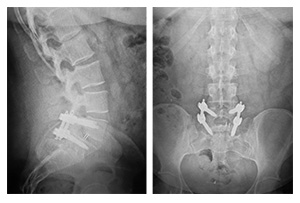

The Primus™ MIS Spinal Fixation System delivers versatility and efficiency through the power of adaptability in a compact, modular system. This minimally invasive modular screw system provides a vast array of implants engineered to work efficiently with intuitive instrumentation for a streamlined, consistent solution. The 5.5/6.0mm MIS system offers a multitude of multi-axial pedicle screws, self-tapping dual-lead cannulated, and diameters from 4.5mm to 8.5mm and lengths from 35mm to 55mm.